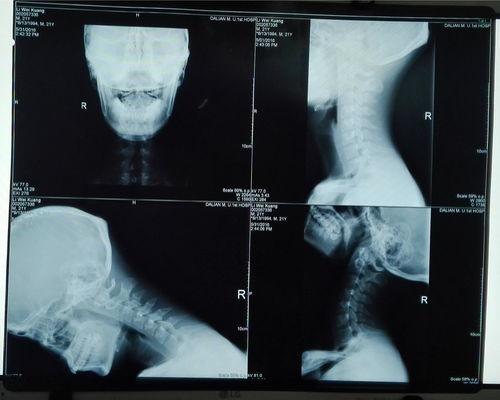

首先,得先认识一下这位“小宝贝”——胸椎。它位于脊椎的中间部分,共有12块椎骨组成。别看它小,作用可大了去了。胸椎不仅支撑着上半身,还负责保护脊髓,连接着颈椎和腰椎。所以,保持胸椎的健康,对整个脊椎系统来说至关重要。